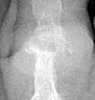

Gout: Erosions 1st MTP joint with preservation of joint space

+ ++